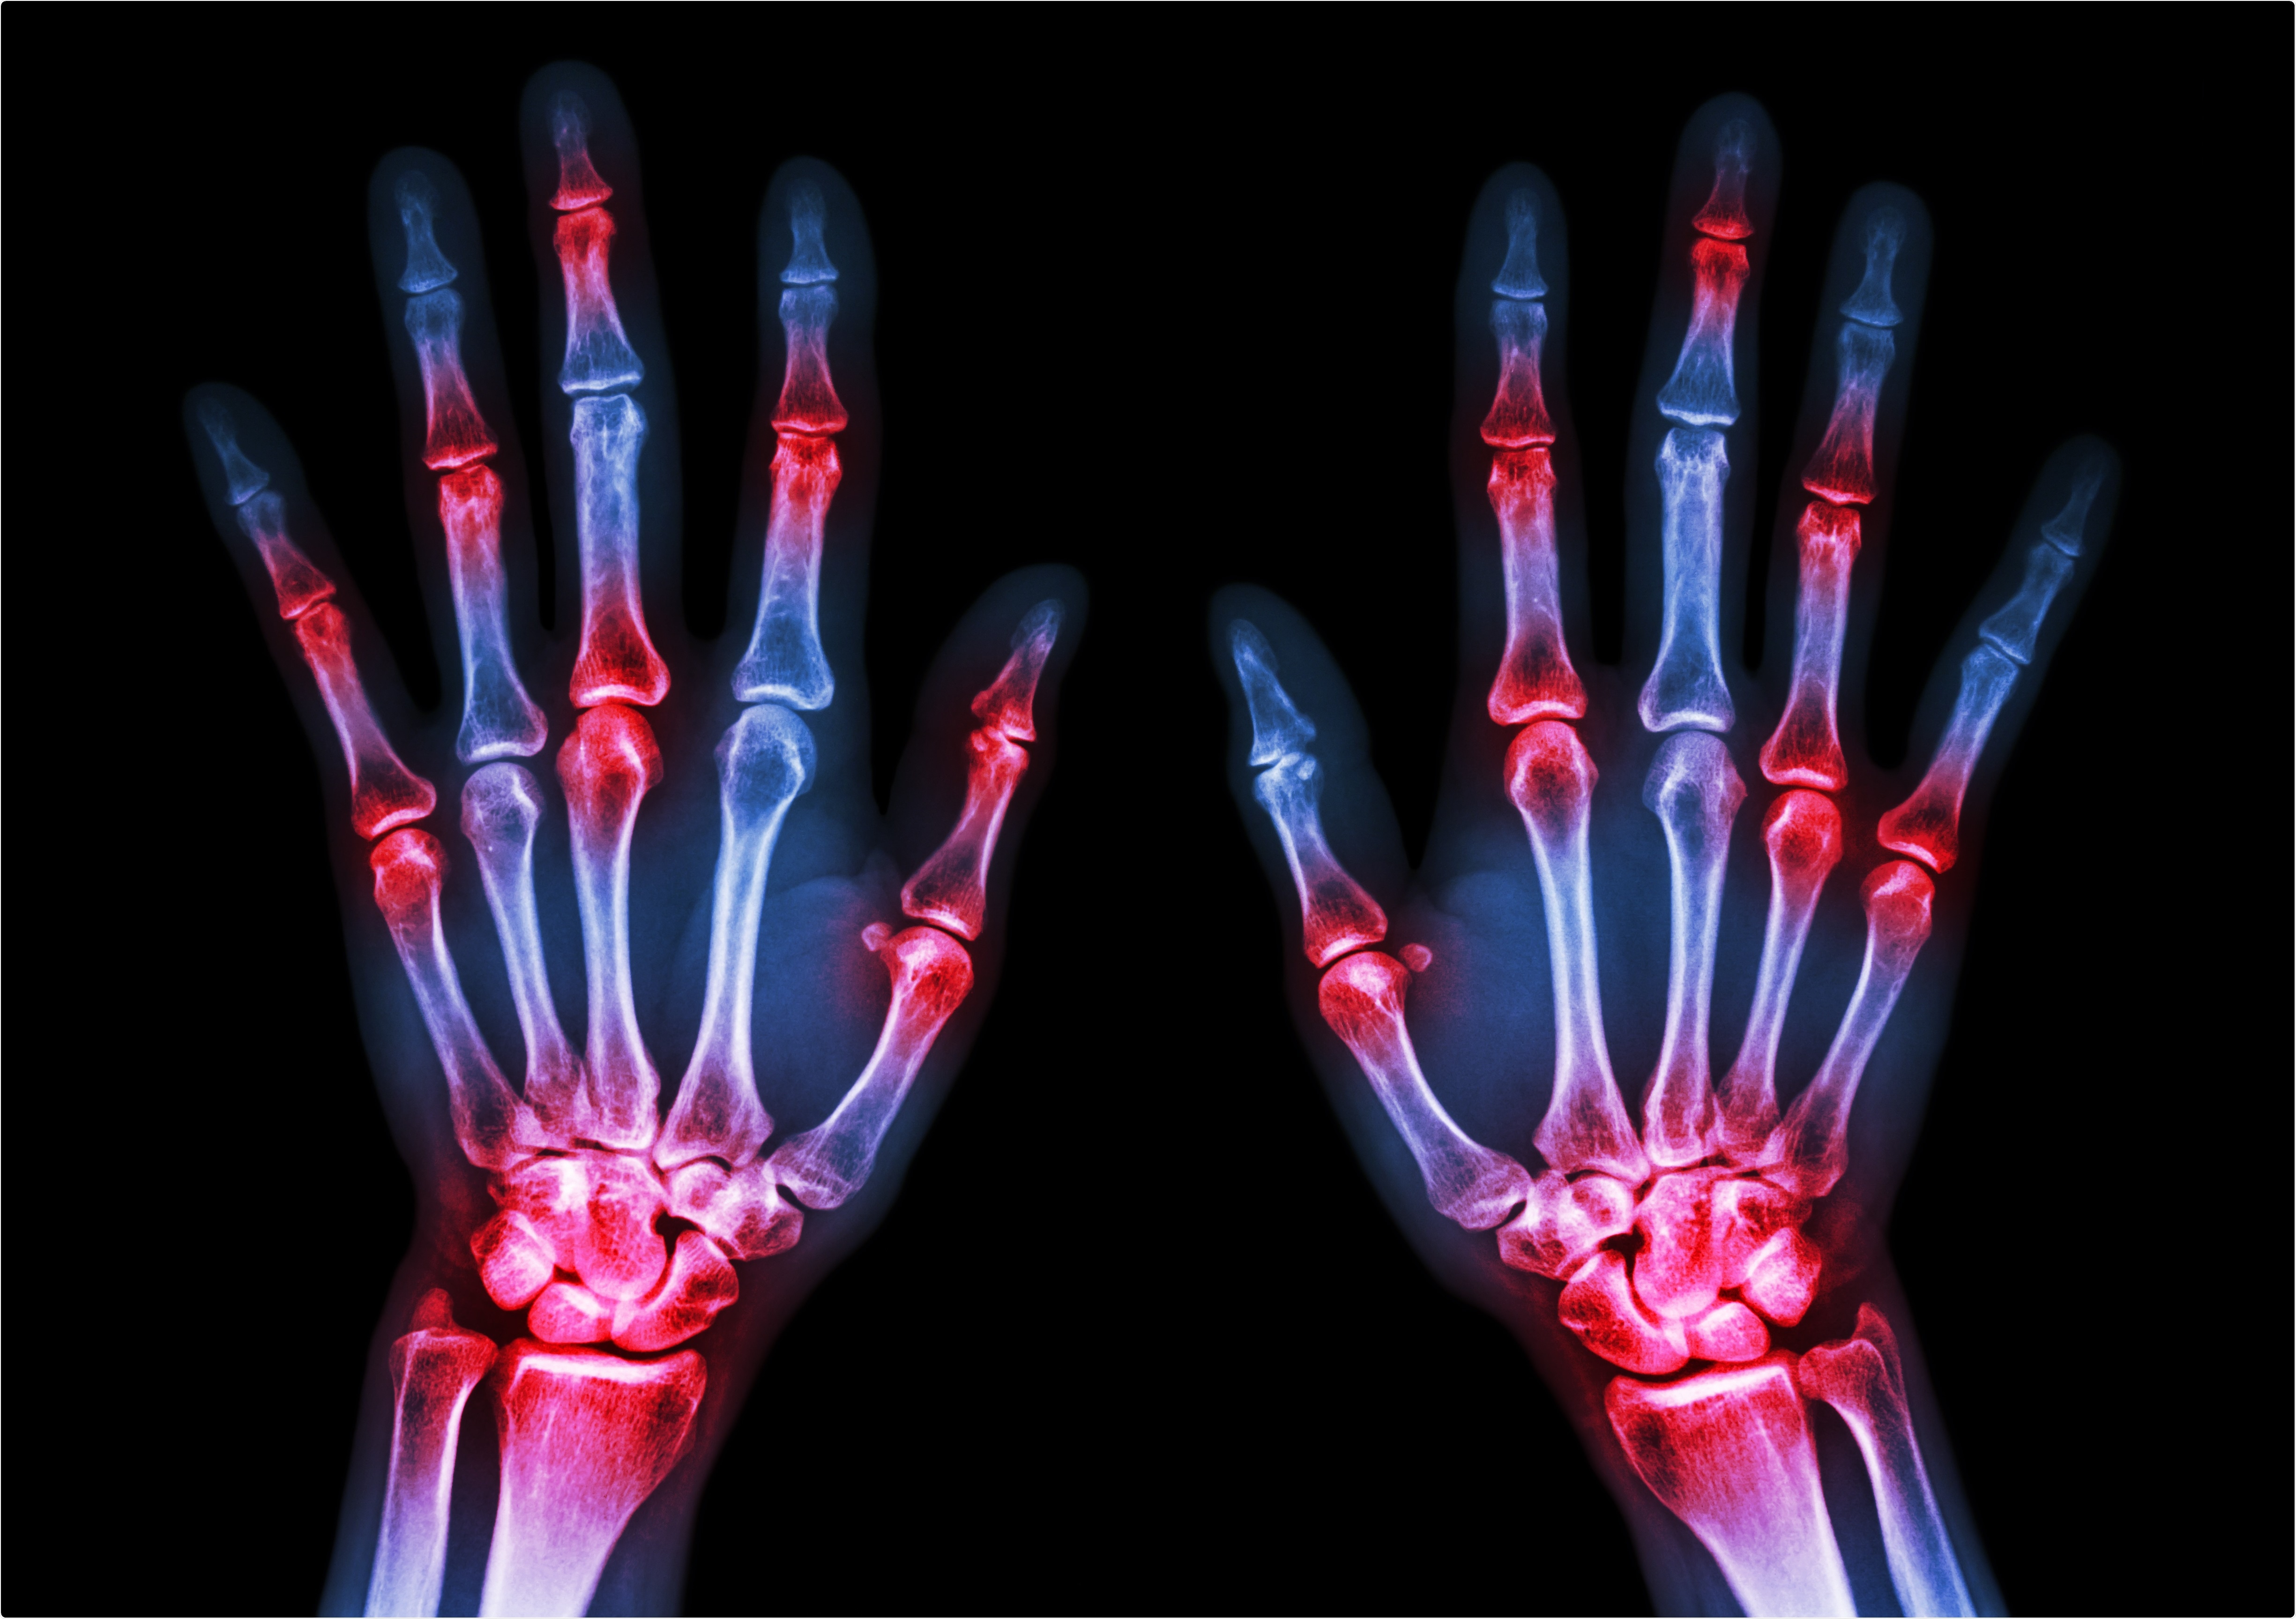

Study: Gout, rheumatoid arthritis and the risk of death from COVID-19. Image Credit: Puwadol Jaturawutthichai / Shutterstock